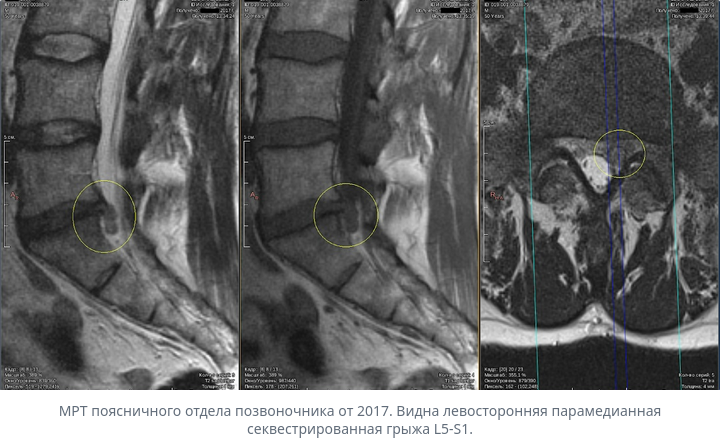

Хорошая новость: грыжа межпозвоночного диска часто сама рассасывается без операции. Организм воспринимает выпячивание диска как инородное тело и постепенно его разрушает и выводит. Это называется резорбция (от слова «рассасывание»).

Такое рассасывание происходит у 70–77% пациентов, которые придерживаются консервативного лечения (без операции). Для крупных грыж, которые отделились и выступают в спинномозговой канал, вероятность ещё выше — до 96%.

На снимке МРТ этот процесс можно увидеть по кольцевидному усилению сигнала вокруг грыжи — это видны кровеносные сосуды, которые прорастают в грыжу.

- Большой размер грыжи (парадоксально, но крупные грыжи часто рассасываются быстрее, так как лучше контактируют с кровеносными сосудами).

- Полный разрыв оболочки диска — это помогает сосудам и иммунным клеткам достичь грыжи.

- Интенсивное кровоснабжение вокруг грыжи (видно на МРТ).